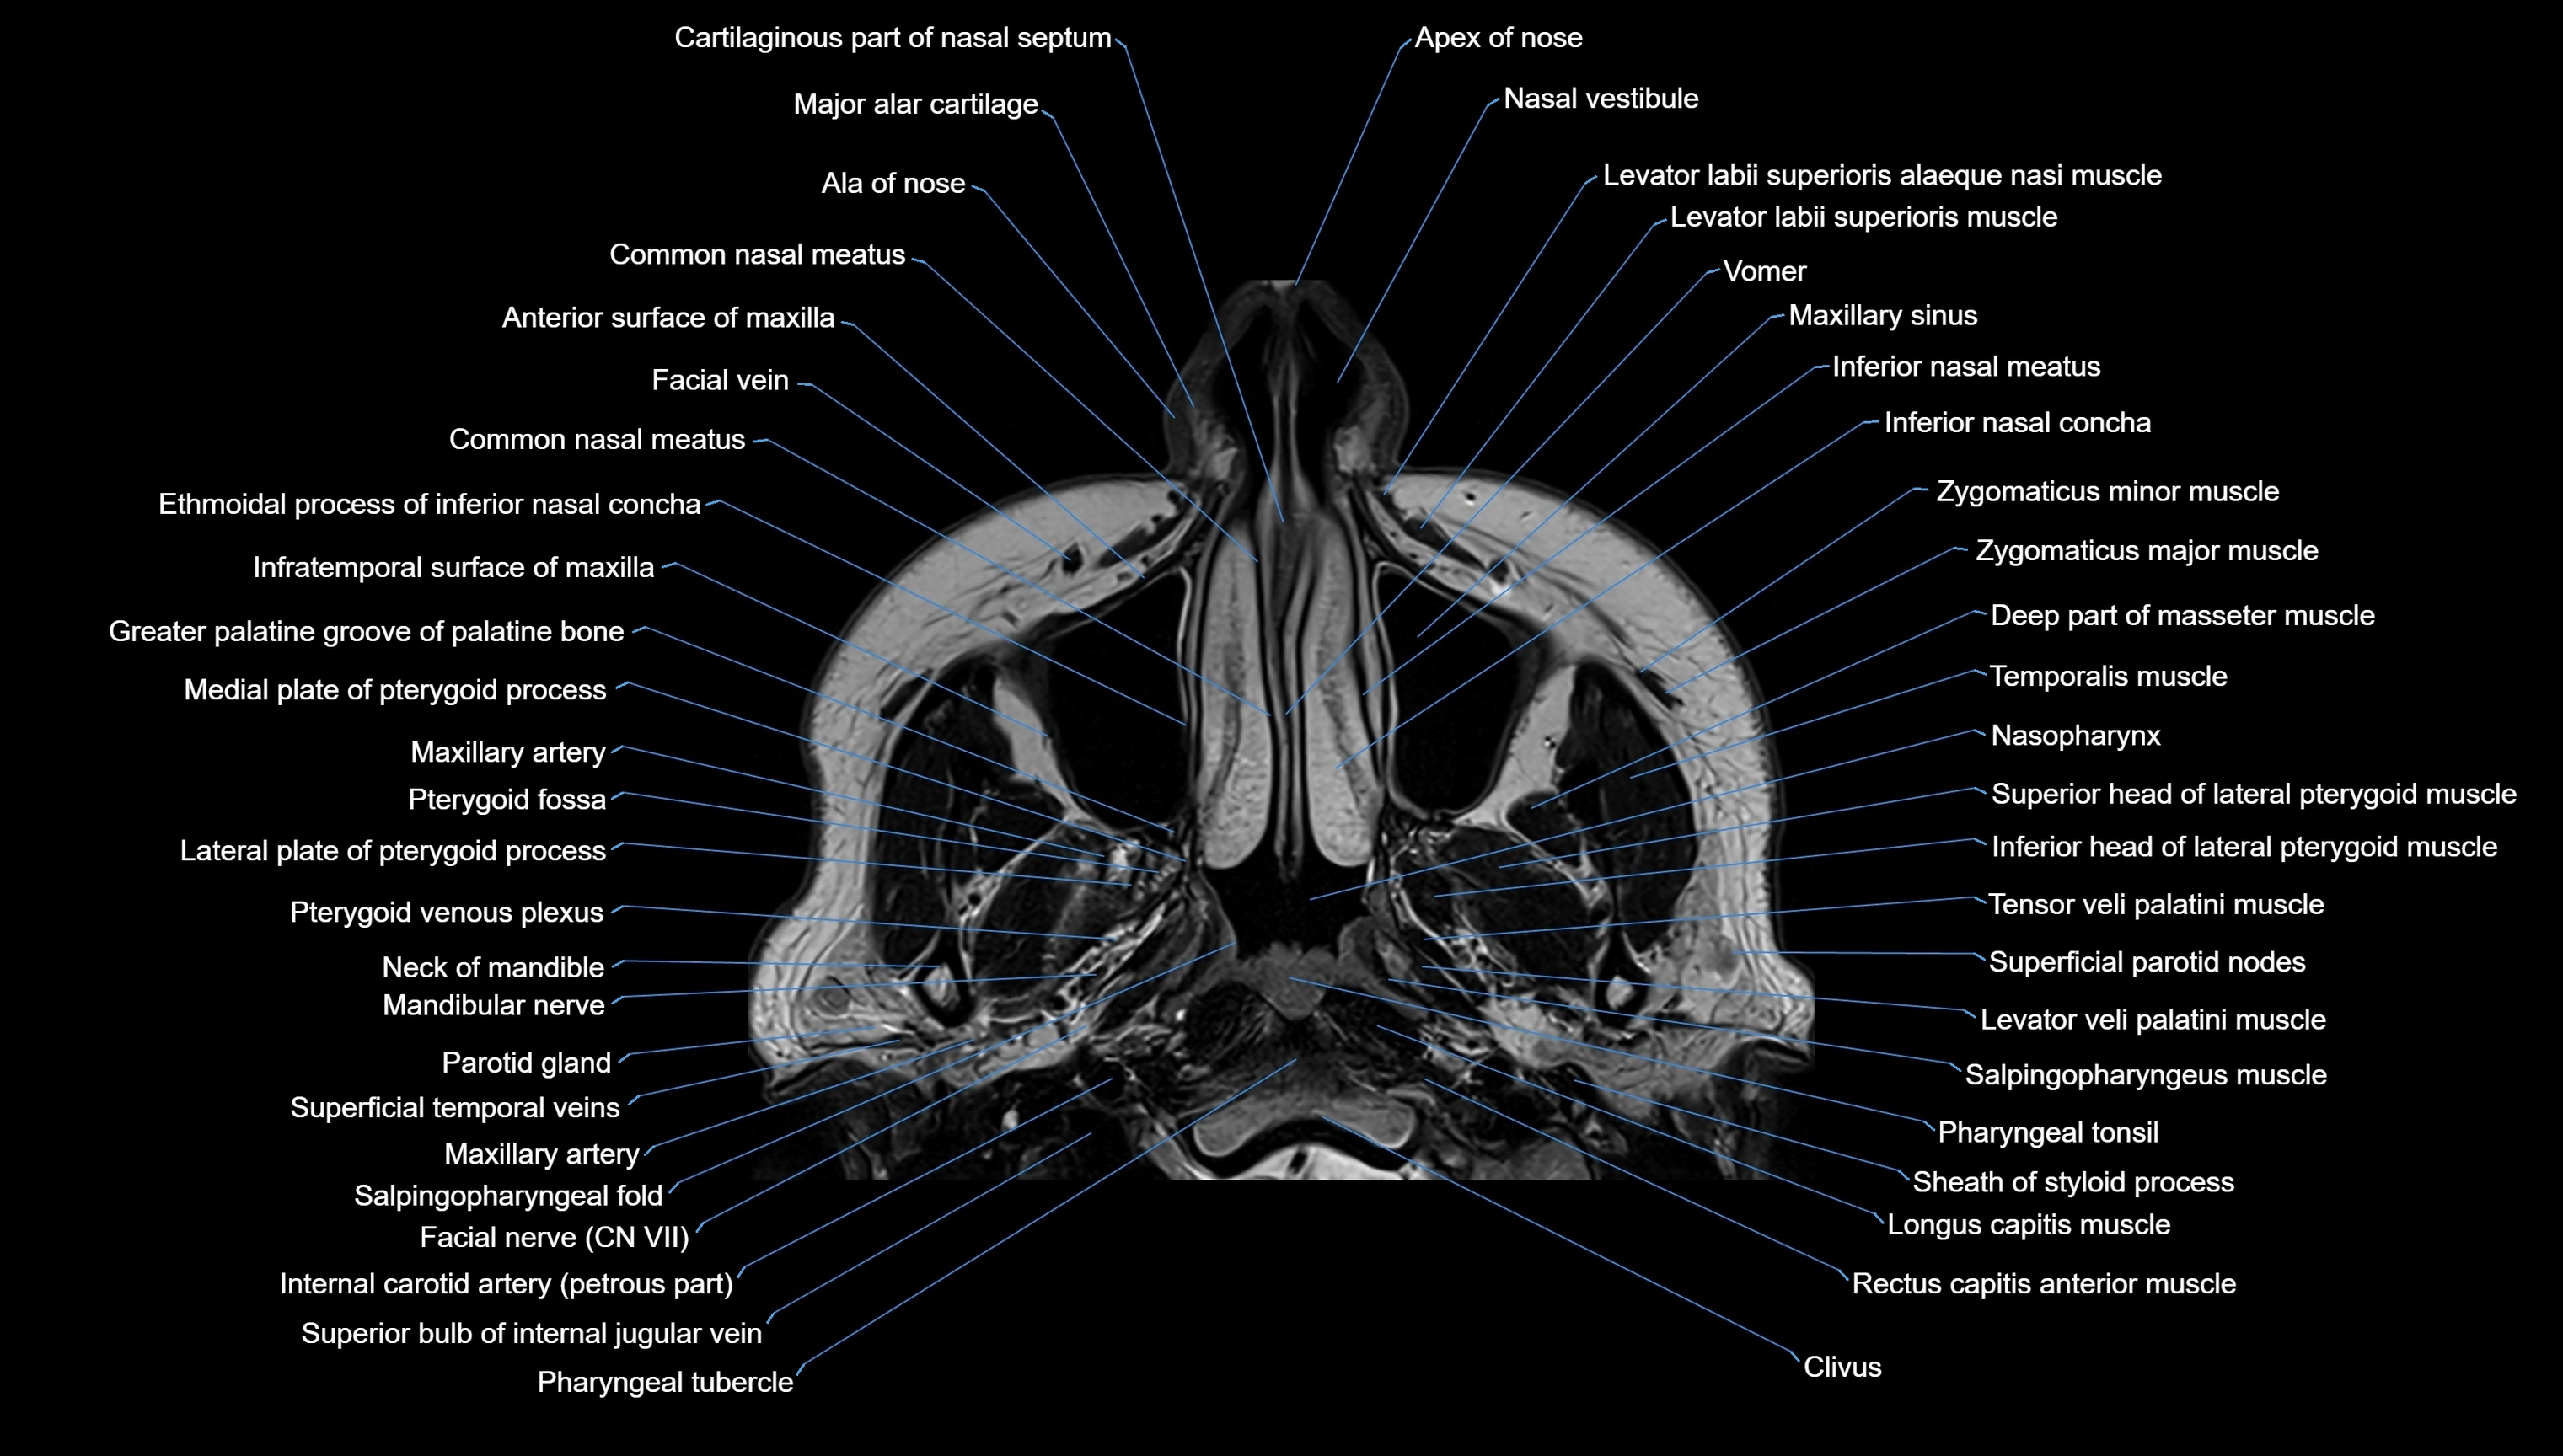

- Apex of nose

- Cartilaginous part of nasal septum

- Common nasal meatus

- Inferior nasal concha

- Inferior nasal meatus

- Levator labii superioris alaeque nasi muscle

- Levator labii superioris muscle

- Major alar cartilage

- Nasal vestibule

- Nasopharynx

- Pterygoid venous plexus

- Rectus capitis anterior muscle

- Superior bulb of internal jugular vein

- Vomer